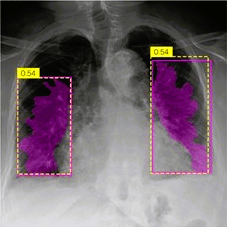

In our recent pilot study, Quantori introduces a two-stage workflow that detects radiographic features associated with pulmonary edema, particularly cephalization, Kerley lines, pleural effusion, bat wings, and infiltrates.

The initial stage isolates the lung area within a radiographic image, ensuring that future decision-making focuses solely on the regions of interest. The subsequent stage focuses on the detection of edema-related features. However, each pulmonary edema feature is highly distinct from the rest, meaning developing a global solution would require a complex and bloated model exceeding realistic limits for use in real-life clinical settings.

Radiological features of pulmonary edema: Cephalization: cyan polylines; Kerley lines: green lines; Pleural effusions: purple masks; Infiltrates: blue masks; Bat wings: yellow masks

To overcome such limitations, Quantori developed a modular approach where each edema feature would be detected by a distinct model. To achieve this, multiple standard ML models were tested, with special attention given to model size (measured in terms of model parameters). A thorough assessment of different architecture pitfalls and model performance was provided. This ensures that trade-offs between model performance and feasibility of application in a real-life setting can be assessed.